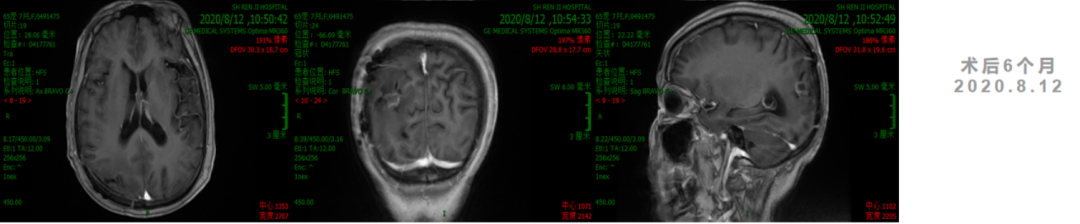

诊疗经过

2. 2020年7月1日起,行TTFields治疗+TMZ 6周期。